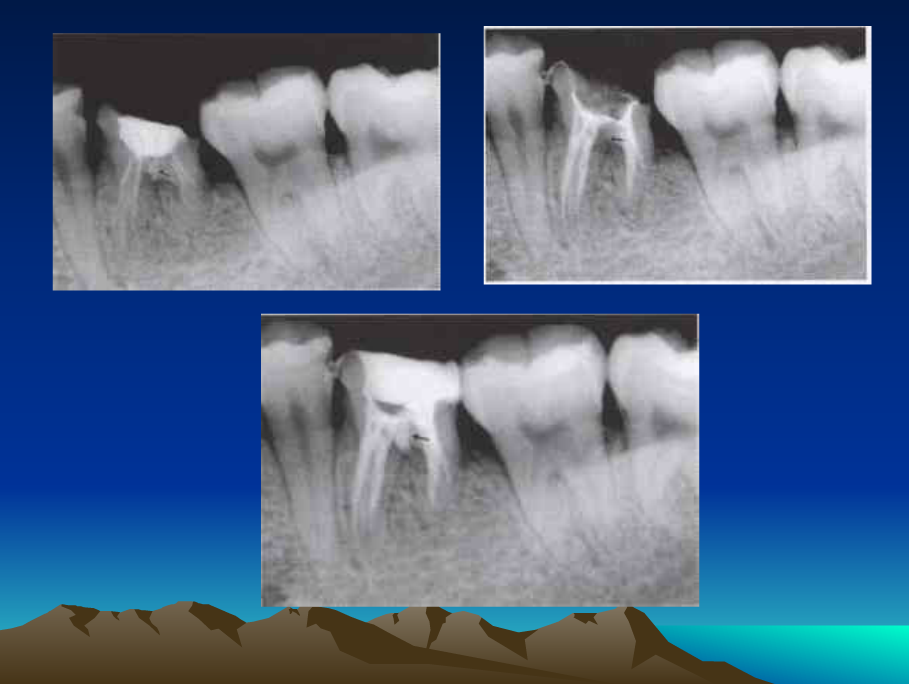

鈣化細(xì)小根管的處理技巧